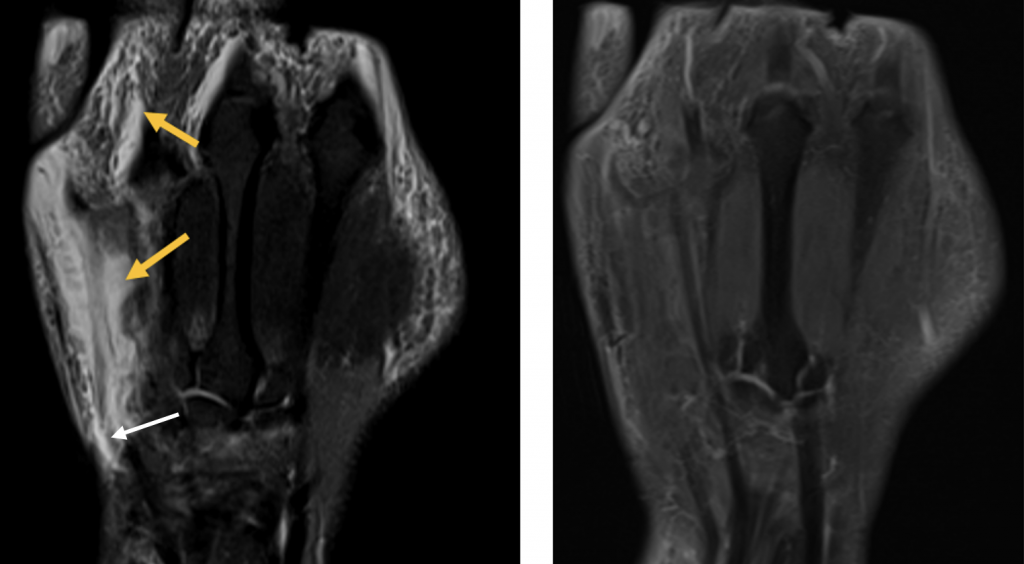

- Ausgeprägte Tenosynovitiden, v.a. der Flexorensehnen (Pfeile) (T1 FS KM)

- Erosion oder kleine Zyste im MC-5 Köpfchen (kurzer Pfeil) und Knochenmarködem im Os hamatum (langer Pfeil) T1 FS KM

- Synovitis der MCP D5, PIP und DIP Gelenke D5 (Pfeile) (T1 FS KM)

- Diffuses Weichteilödem entlang des 5. Strahles mit korrespondierender KM- Aufnahme (Pfeile) (T1 FS KM)

- Zusätzliche diffuse ödematöse Veränderungen im Subkutangewebe der gesamten Hand (Pfeile) mit fehlender oder nur sehr wenig korrespondierender KM Aufnahme